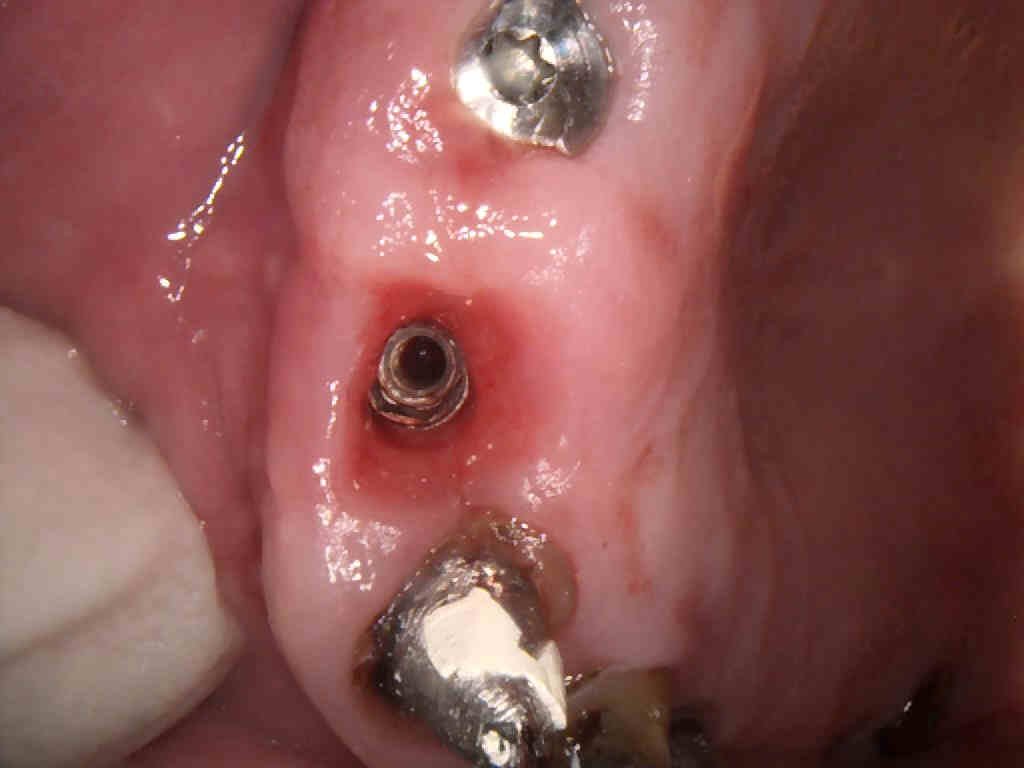

Buenas tardes, Adjunto radiografía periapical con y sin tapón de cicatrización y foto de la conexión interna. El tapón de cicatrización es de Straumann pero no parece ser su tapón. [...]